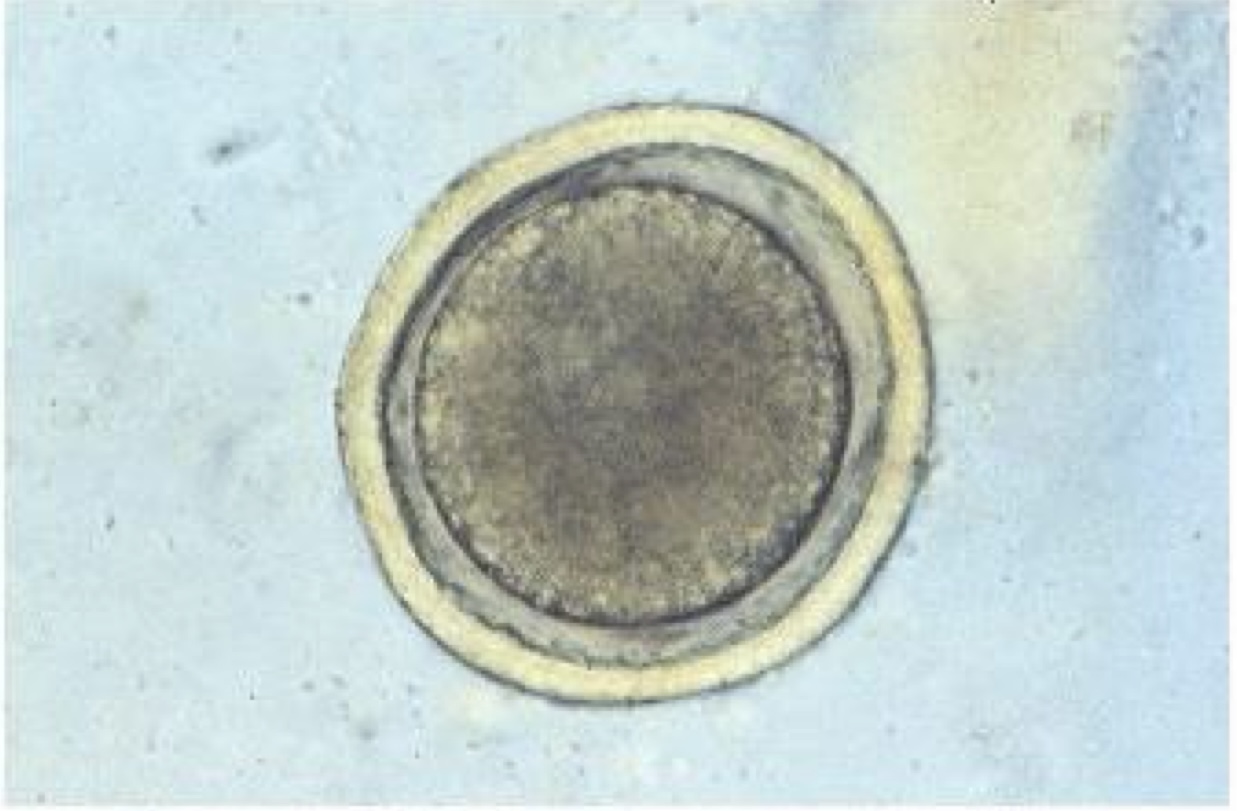

characteristics of a Toxocara species

C/S : vomiting, diarrhea, constipation

ZOONOTIC

paratenic hosts: rodents, rabbits

prevention: hygiene, deworming

treatment: Fendendazole

route of transmission: ingestion of infected egg

Dx technique: fecal flotation